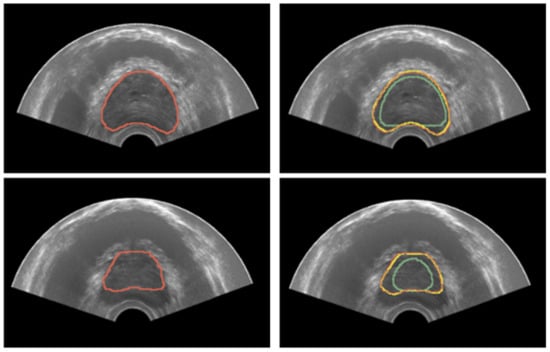

3.2. Registration

Quantitative results for registration across the two considered imaging modalities, TRUS and MRI, are reported in Table 4 for the configurations with and without landmarks, respectively. An example of the workflow for the image fusion is depicted in Figure 10. Dice Coefficient is higher than 91% for all the cases, and HD is less than 4 mm, demonstrating that the developed registration method is promising.

Figure 10.

Workflow employed for the image-fusion procedure. Segmentation masks are obtained for both domains—TRUS and imaging. Then, the registration is performed as described in Section 2.5, so that images can be fused. Both masks are shown after the registration procedure.